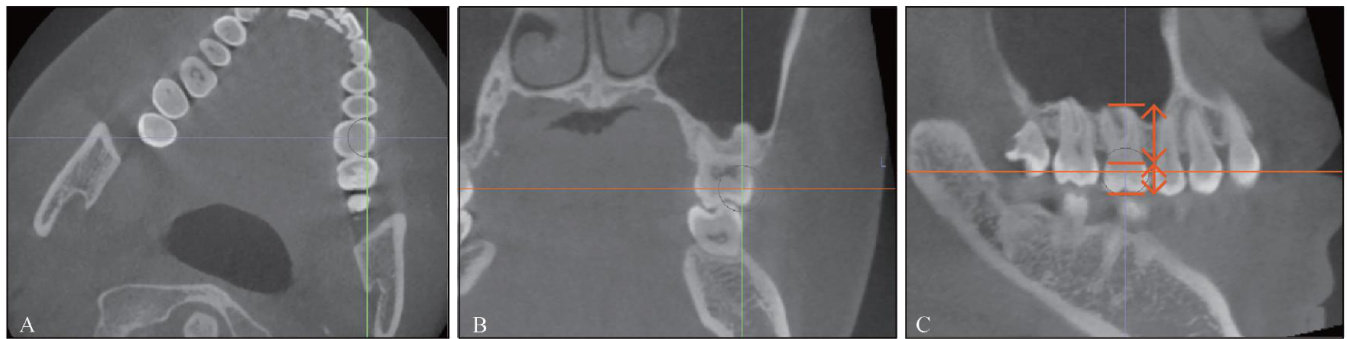

[摘要]目的探究无托槽隐形矫治(CAT)过程中上颌扩弓效率的影响因素。方法筛选54名上颌扩弓矫治的非拔牙CAT患者,收集其基线数据,通过锥形束计算机断层扫描(CBCT)测量其牙冠和牙根长度,模型重叠测量其上颌扩弓效率和转矩变化,通过线性分析探究影响扩弓效率的因素。结果单因素线性分析中发现,年龄、牙根长度、冠根比、附件设计、设计扩弓量和实际-设计转矩变化对上颌第一磨牙扩弓效率有影响( (P<0.05) 。逐步多因素线性分析中发现,冠根比、16和26牙的实际-设计转矩对上颌第一磨牙扩弓效率有显著影响( (P<0.05) 。结论在CAT扩弓矫治过程中,需要注意患者的冠根比,设计方案时需要双侧磨牙设计附件并注意扩弓量的限制,以增加患者扩弓效率。